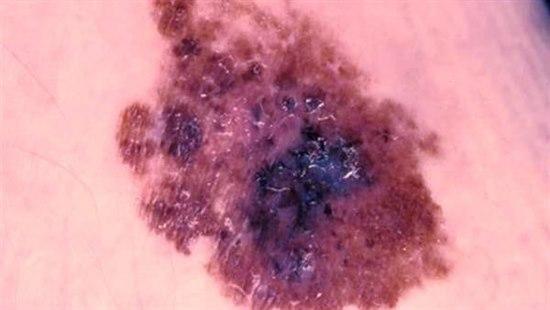

Ny behandling mot metastatisk melanom

Det har vært en betydelig økning i behandlingsalternativer ved metastatisk melanom. Et nytt behandlingsprinsipp viser lovende resultater.